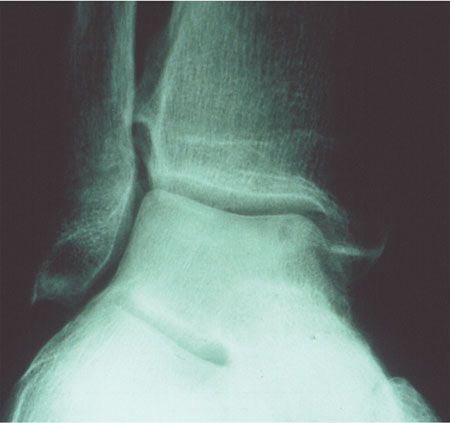

Pédagogie Les séquelles des entorses externes de la cheville , Jacques Rodineau 3, avenue Bugeaud, 75116 Paris, France , E. Rolland Service de Chirurgie Othopédique Hôpital de la Pitié 75013 Paris , S. Besch SAU Hôpital de la Pitié 75013 Paris , Jean-François Kouvalchouk Hôpital Foch, Suresnes, France N°138 - Novembre 2004 ● 9 min de lecture